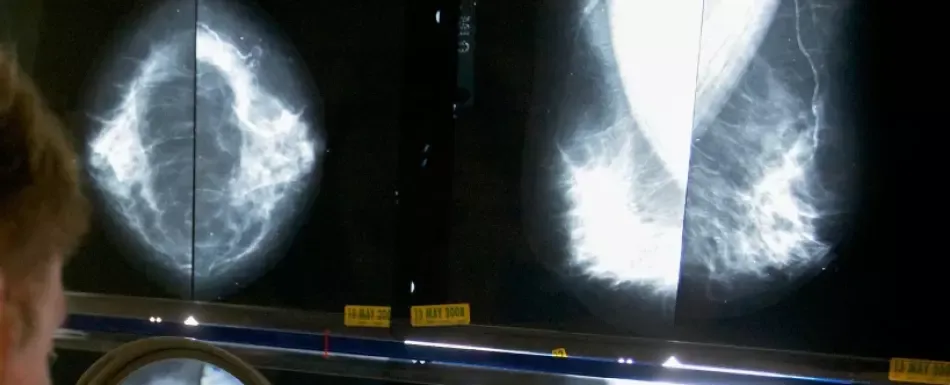

Durante los primeros años de la pandemia de COVID-19, los expertos temían que las interrupciones en el diagnóstico y tratamiento del cáncer costarían vidas. Un nuevo estudio sugiere que tenían razón. El estudio financiado por el gobierno estadounidense y publicado el jueves por la revista médica JAMA Oncology sería hasta ahora el primero en evaluar los efectos de las interrupciones relacionadas con la pandemia en la supervivencia a corto plazo de los pacientes oncológicos. Los investigadores encontraron que las personas diagnosticadas con cáncer en 2020 y 2021 tuvieron una peor supervivencia a corto plazo que aquellas diagnosticadas entre 2015 y 2019. Esto fue cierto en una variedad de tipos de cáncer, independientemente de si fueron diagnosticados en una etapa tardía o temprana. Por supuesto, el coronavirus en sí mismo fue especialmente peligroso para los pacientes ya debilitados por el cáncer, pero los investigadores trabajaron para filtrar las muertes atribuidas principalmente al coronavirus, para poder ver si otros factores jugaron un papel. Los investigadores no pudieron demostrar de manera concluyente qué causó una menor supervivencia, dijo Todd Burus de la Universidad de Kentucky, autor principal del estudio. “Pero las interrupciones en el sistema de salud probablemente fueron un factor clave”, expresó Burus, quien se especializa en análisis de datos médicos. El COVID-19 obligó a muchas personas a posponer exámenes de detección de cáncer —colonoscopias, mamografías y escaneos pulmonares— ya que el coronavirus saturó a los médicos y hospitales, especialmente en 2020. Investigaciones anteriores habían mostrado que las tasas generales de mortalidad por cáncer en Estados Unidos continuaron disminuyendo durante la pandemia, y no hubo grandes cambios en los diagnósticos tardíos. Recinda Sherman, investigadora de ese trabajo anterior, aplaudió el nuevo estudio. “Como este estudio es el primero en documentar la supervivencia específica por causa relacionada con la pandemia, creo que es importante”, manifestó Sherman, de la Asociación Norteamericana de Registros Centrales de Cáncer. “Cuanto más entendamos sobre el impacto del COVID-19, mejor podremos prepararnos para la próxima vez”. ¿Cómo podrían las tasas generales de mortalidad por cáncer disminuir en 2020 y 2021, mientras que la supervivencia a corto plazo empeoró para los pacientes recién diagnosticados? Las medidas de prevención, diagnóstico y tratamiento del cáncer que durante años ayudaron a reducir las tasas de mortalidad por cáncer no desaparecieron repentinamente durante la pandemia, señaló Burus. “No olvidamos cómo hacer esas cosas”, dijo. “Pero las interrupciones podrían haber cambiado el acceso, podrían haber cambiado la rapidez con la que las personas estaban recibiendo tratamiento”. Más investigaciones mostrarán si algún impacto fue duradero, comentó Hyuna Sung, científica principal y epidemióloga en la Sociedad Americana del Cáncer. “Las disminuciones transitorias en la supervivencia que se recuperan rápidamente pueden tener poco impacto en las tendencias de mortalidad a largo plazo”, señaló. El nuevo estudio utilizó datos del registro nacional de cáncer para centrarse más específicamente en pacientes que tuvieron un primer diagnóstico de cáncer maligno en 2020 y 2021. Más de 1 millón de personas fueron diagnosticadas con cáncer en esos dos años, y alrededor de 144.000 murieron en el lapso de un año, según los datos de los investigadores. Los investigadores observaron las tasas de supervivencia a un año para esos pacientes, verificando en qué etapa se encontraban al momento del diagnóstico. Calcularon que la supervivencia a un año fue menor tanto para diagnósticos en etapas tempranas como tardías, para todos los sitios de cáncer combinados. Lo más preocupante fueron las grandes diferencias observadas en los cánceres colorrectal, de próstata y de páncreas, dijeron. En general, los investigadores encontraron que más del 96% de las personas que obtuvieron un diagnóstico de cáncer en etapa temprana en 2020 y 2021 —y más del 74% de aquellos con un diagnóstico en etapa tardía— sobrevivieron más de un año. Esas tasas fueron ligeramente más bajas de lo que se habría esperado según las tendencias de 2015-2019, resultando en aproximadamente 17,400 muertes más de lo esperado.